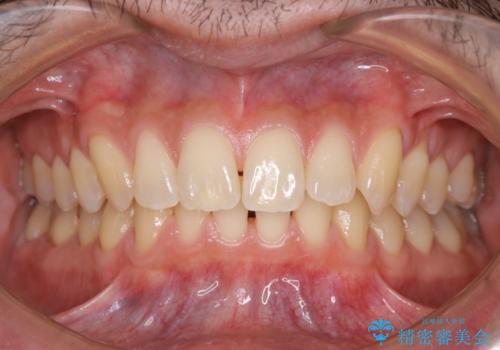

- 数年ぶりに歯科へ来院とのこと。全体的に歯のクリーニングをしてほしいとのことでした。

PMTC60分コースを行いました。

お口のトラブルを予防するには、PMTC(歯科医院で専門的な機械や材料を使用してクリーニング)を定期的に行うことが効果的な治療法です。